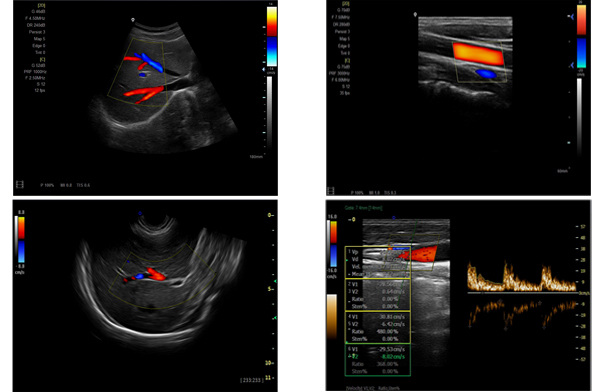

為高集成數(shù)字式彩色多普勒系列產(chǎn)品之一,廣泛實(shí)施于腹部,產(chǎn)科,婦科,血管,小器官,泌尿,新生兒和兒科等臨床,屬全身應(yīng)用型彩色多普勒儀器。

●全身應(yīng)用型包含2D/CFM/PDI/PW/ M等掃描模式;